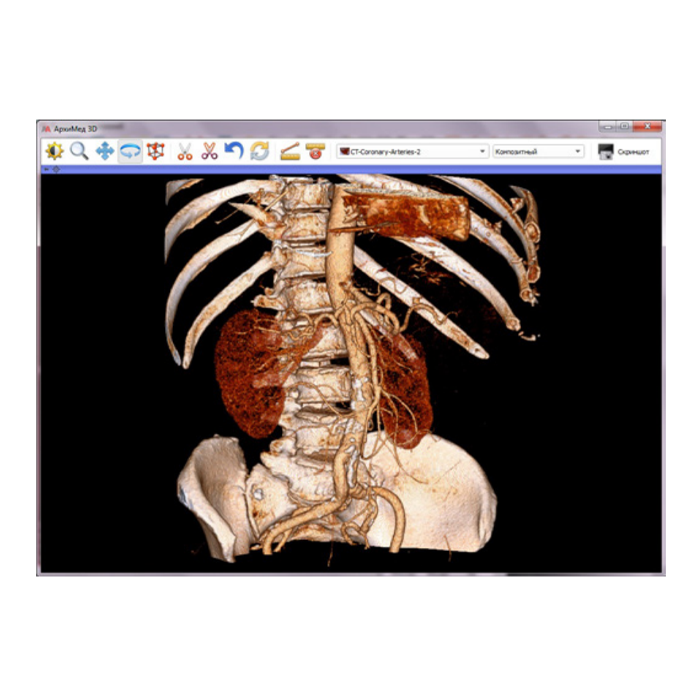

АрхиМед PACS/RIS — это комплексное программное решение для цифровизации и оптимизации работы лучевой диагностики. Система объединяет процессы управления исследованиями (RIS), хранения и обработки медицинских изображений (PACS), а также создания структурированных отчетов. Это фундамент для создания современного, эффективного и безопасного радиологического отделения или целой сети медицинских учреждений.

- Работа с изображениями: Автоматический прием снимков с любого DICOM-совместимого оборудования (КТ, МРТ, рентген, УЗИ и др.), организация единого защищенного архива.

- Повышение качества диагностики: Доступ к полной истории изображений пациента, инструменты для сравнения, точных измерений и постобработки.

| Поддерживаемые модальности | КТ, МРТ, рентген (в т.ч. цифровой), маммография, УЗИ, ангиография и другие DICOM-совместимые аппараты |